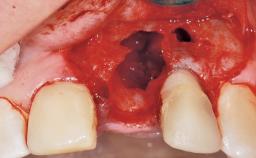

Immediate Flapless Placement of an Implant in a Maxillary Left Central Incisor Site

A 42-year-old female patient was referred to our clinic at the School of Dentistry of the University of São Paulo in November 2004, presenting a deficient restoration in the upper left central incisor. The clinical examination revealed no gingival retraction or any signs of gingival inflammation and, therefore, previous periodontal treatment was not considered. The patient presented a high lip line at full smile and a thin tissue biotype. This combination characterized a high-risk situation from an anatomic point of view, which required careful preoperative planning and cautious surgical execution.

Socket Integrity Sufficient, with intact bone walls

Bone Volume Sufficient, with intact walls